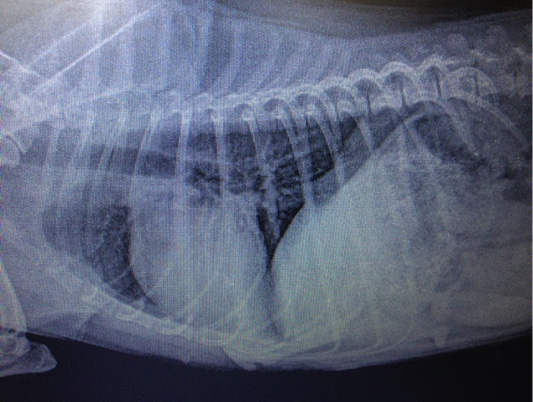

Figure 7

Metastasis of mammary gland cancer in the lungs. Doggess, Miniature Schnauzer, at the age of 10.5 years.